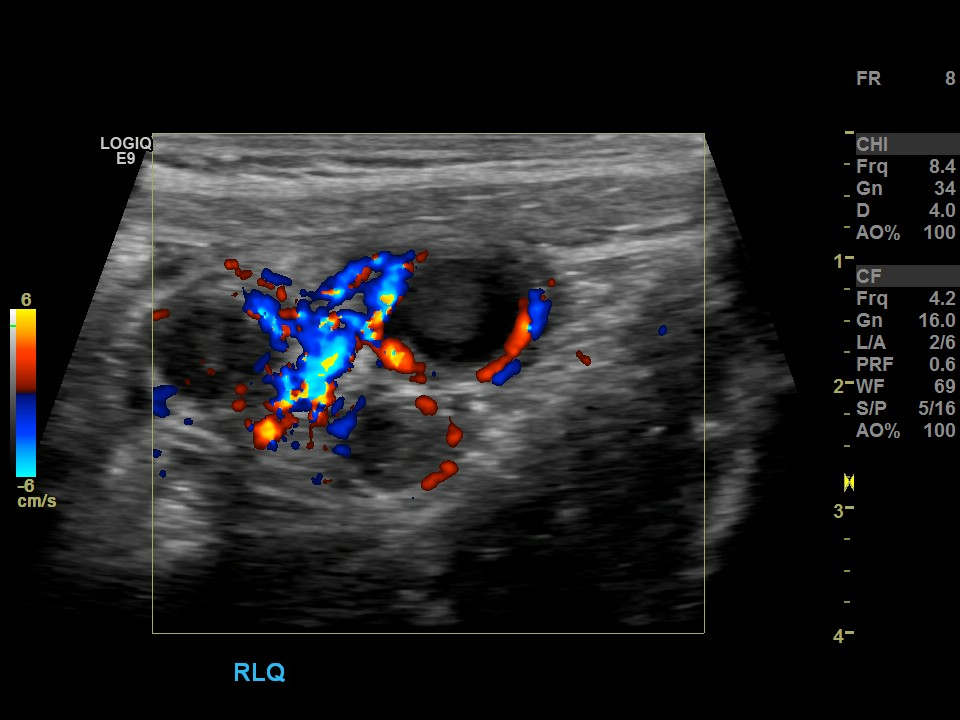

Appendicitis 15

Appendicitis 16

Hyperemia, echogenic fat and appendicolith